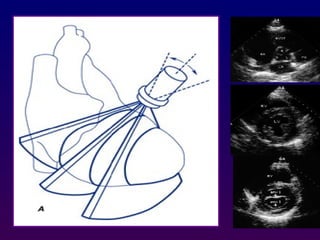

From the PLA orientation, a 90° clockwise rotation of

the transducer with superior and inferior

transducer manipulations permits delineation of the

parasternal short axis (PSA) views:

Parasternal short axis

70°to 110° clockwise

a 90° clockwise rotation

At the basal (aortic valve) level, the right atrium, septal

and anterior leaflets of the tricuspid valve, right

ventricular free wall, right ventricular outflow tract,

pulmonic valve, main pulmonary artery, and left

atrium can be seen "surrounding" the centrally

oriented aortic valve.

All three leaflets of the aortic valve may be identified,

forming a "Y" configuration during ventricular

diastole and "upside-down triangle" during

ventricular systole

Slightly inferior angulation mitral valve

level appears and the mitral orifice has a

characteristic "ovoid" or "fish-mouth"

appearance. the anterior mitral leaflet is

located superiorly.

- Slightly more inferior angulation results

in visualization of the contracting left

ventricle at the papillary muscle level ,

-More inferior angulation will visualize LV

at apex level